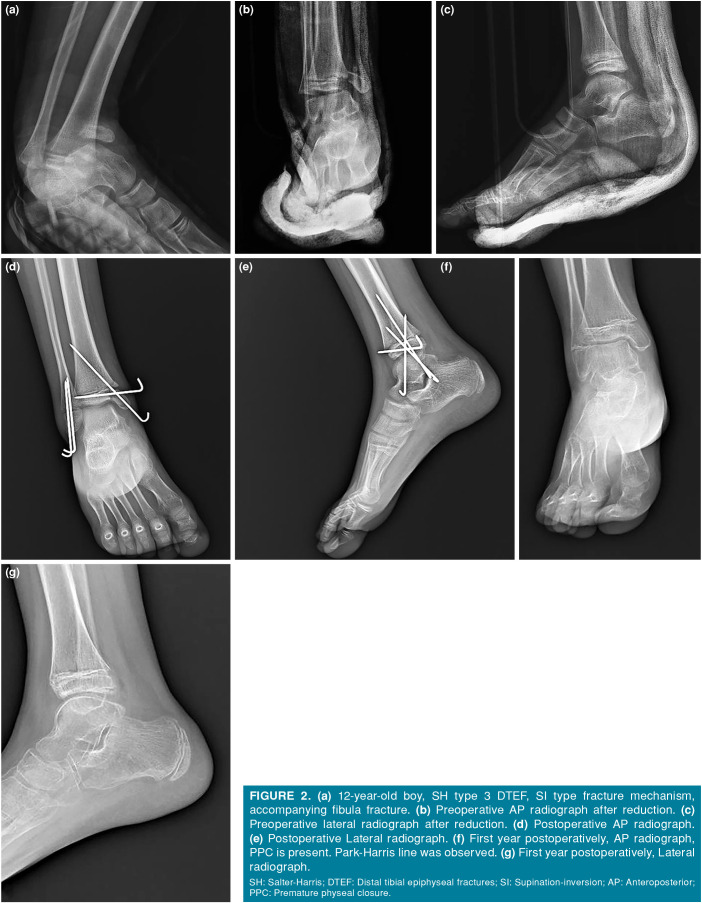

Patients and methods: Between January 2015 and January 2021, a total of 46 patients (37 males, 9 females; mean age: 11.9±2.5 years; range, 6 to 16 years) who were operated within 12 h due to displacement >2 mm after reduction were retrospectively analyzed. Demographics, fracture type (Salter-Harris [SH]), fracture mechanism (Dias & Tachdjian [DT]), accompanying fibula fracture, and initial displacement were assessed with preoperative radiographs. At two years of follow-up, PPC, angular deformity, and length discrepancy were evaluated.

Results: Of the patients, PPC was observed in 21.7%. Angular deformity and length discrepancy were noted in 6.5% of cases. The average initial displacement was 6.8 mm, with no significant correlation between displacement and complications (p>0.05). While the rates of PPC varied by fracture type, there was no statistically significant relationship between fracture types and the development of complications (p>0.05). Premature physeal closure was more common in fractures caused by the supination-plantar flexion (SPF) mechanism (60%) compared to the pronation-eversion external rotation (PEER) mechanism (5.3%) (p=0.018). Angular deformity and length discrepancy were only associated with SH type 3 and 4 fractures. Although fibular fractures accompanied 25% of distal tibial epiphyseal fractures, their presence did not show a significant correlation with complications (p>0.05).

Abstract Image